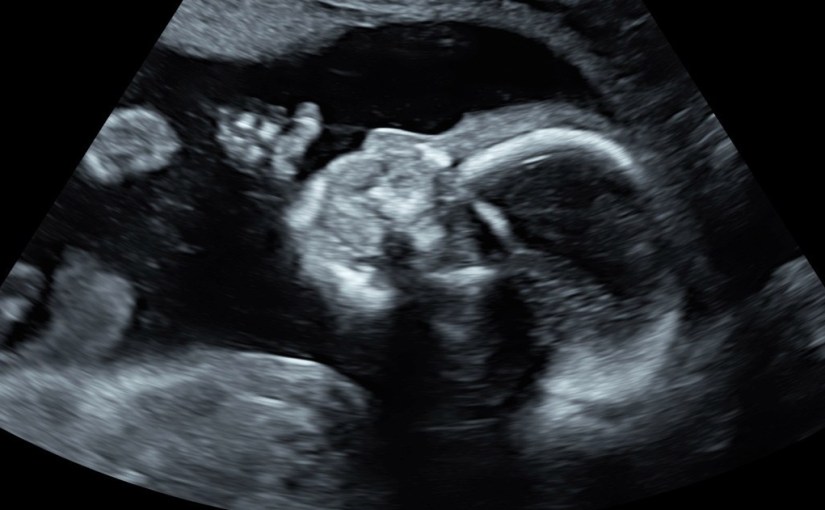

one of my best friends stepped in for Mike and took me to the appointment and was my nurse for the rest of the day. the ultrasound showed the amniotic walls were fused and the procedure could take place. i think the entire procedure took all of one minute. it was definitely uncomfortable and not something i would like to do again. we had to wait two weeks for the results.